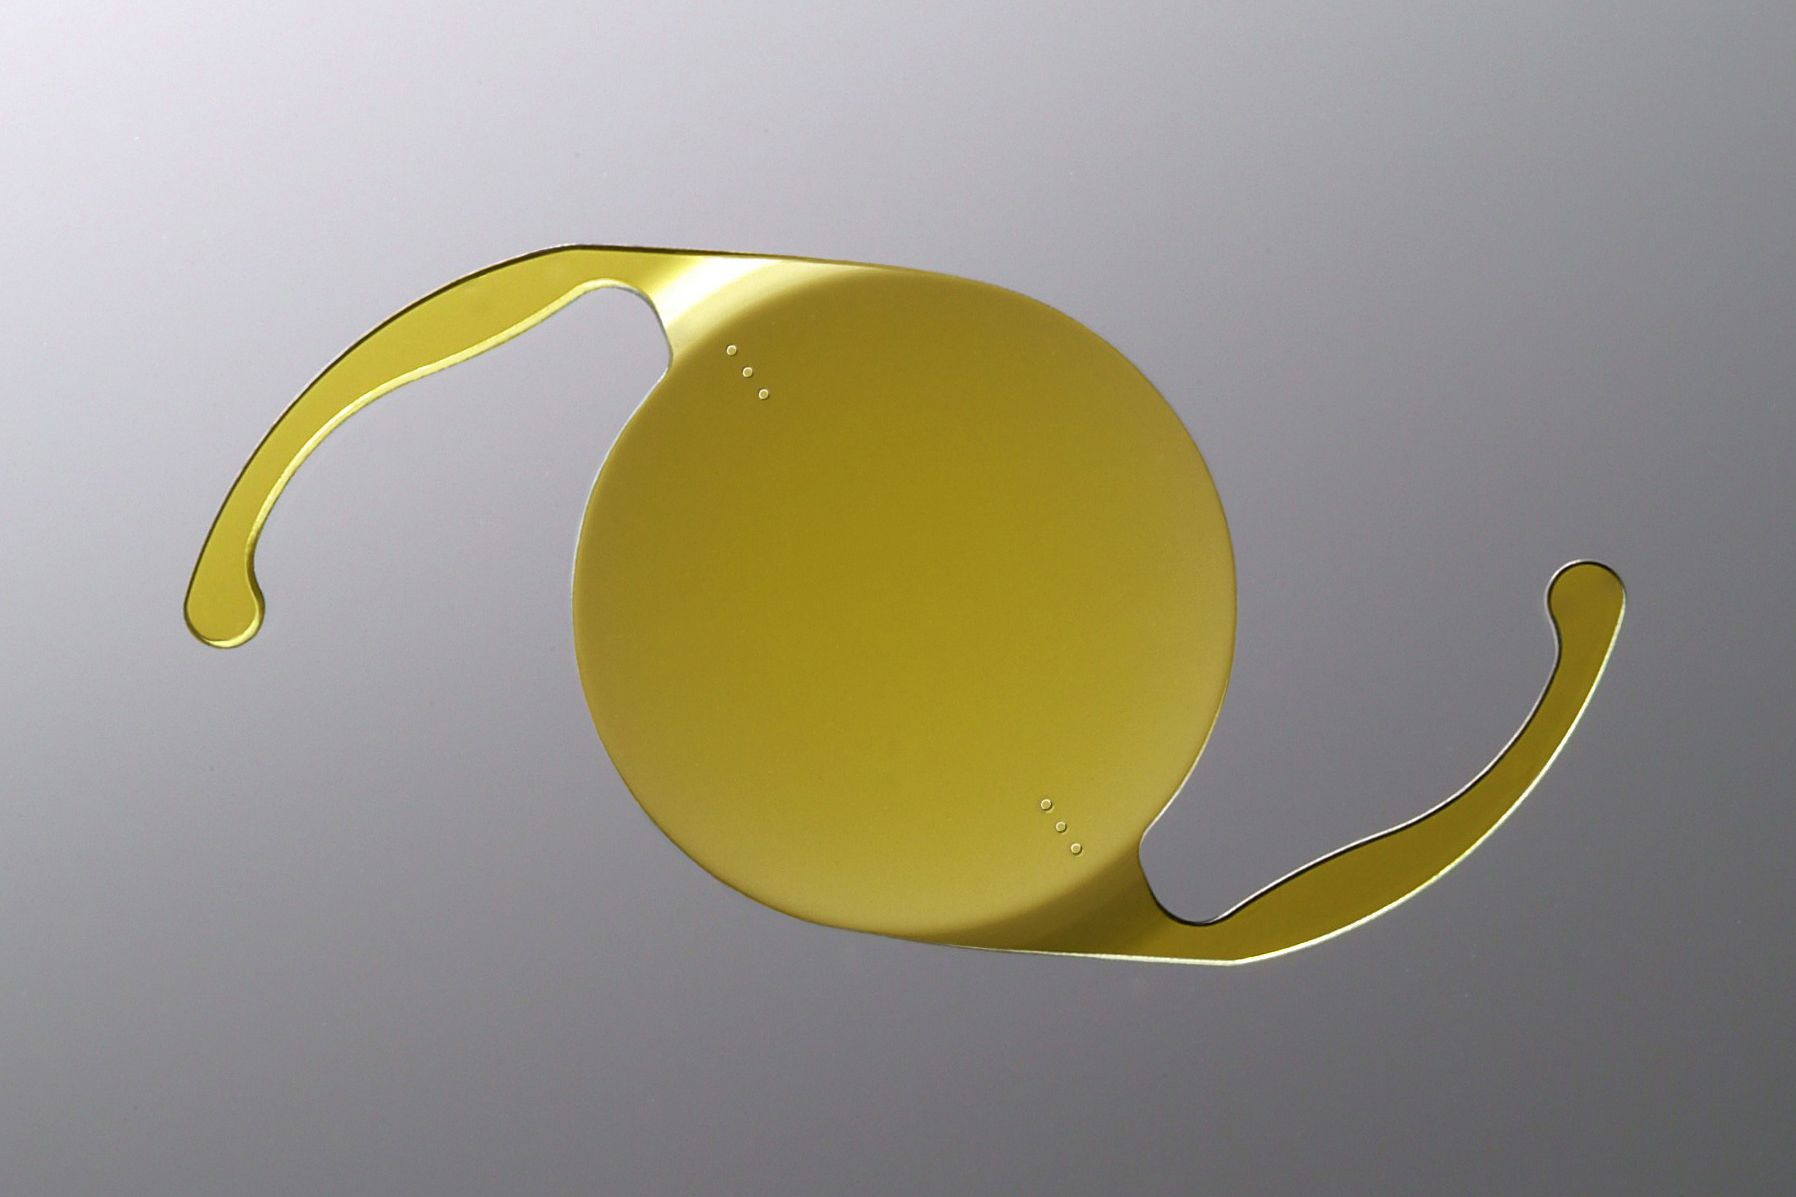

During cataract surgery, an intraocular lens (IOL) is used to replace the eye's natural, clouded lens. Dr. Walter Choate provides several types of IOLs at our Goodlettsville, TN, optometrist's office. It is important to understand the various benefits that these devices offer. During a thorough consultation, our team can find the IOL that is best suited to your unique preferences and needs.

An IOL is a medical device which acts a replacement for natural lenses clouded by cataracts. IOLs typically fall into one of two categories:

Both multifocal and accommodating lenses allow patients to see clearly at near, intermediate, and far distances. Many patients who choose these IOLs do not need corrective eyewear after surgery and report particularly clear vision while using computers and handheld devices. Multifocal IOLs achieve this flexibility in their structure while accommodating IOLs work with the muscles in the eye to change focus.

- AcrySof® IQ ReSTOR®: This multifocal IOL features a series of tiered steps to help patients see clearly at a range of distances.

- Crystalens®: An accommodating IOL, Crystalens® bends and flexes like a natural lens. Cataract or presbyopic patients can adjust to a large range of distances with this option.